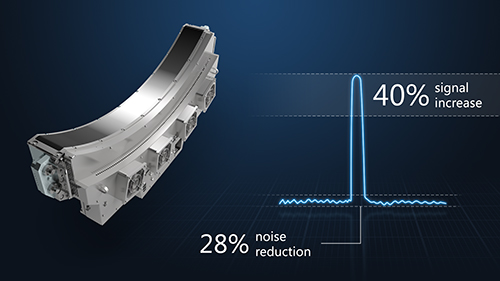

Новый детектор PURE ViSION

Технология PURE ViSION Detector, которая была внедрена в системы